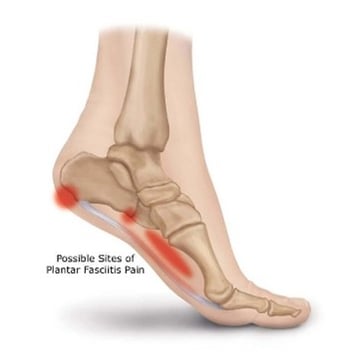

Plantar Fasciitis Plantar Fasciitis is a common and often debilitating condition of the foot found in both male and females. If addressed promptly and properly, rarely should it need surgical intervention to fix. There are many factors that can lead to this...